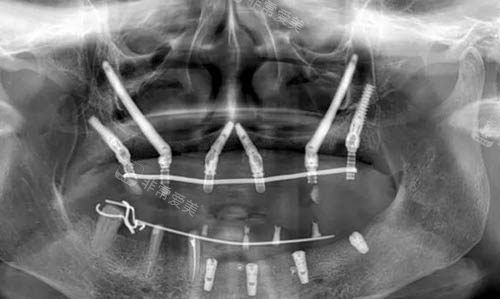

穿颧穿翼种植ct照片

穿颧穿翼种植技术有哪些优势?

穿颧穿翼种植是针对骨量重度不足人群的“救星技术”,牛凯医生在这一领域的技术优势十分突出。

适应复杂骨条件:传统种植需要足够骨量,而穿颧穿翼种植可直接将种植体植入颧骨或翼板等骨密度高的部位,即使牙槽骨重度萎缩、骨量不足,也能实现稳定固位,避免植骨手术的痛苦和时间成本。

手术时间短、改善快:牛凯医生通过智能化导航更准一些定位,单颗穿颧/穿翼种植手术时间可控制在30-60分钟,术后肿胀轻,多数顾客3-7天即可正常进食,大大缩短了改善周期。

咀嚼力接近真牙:种植体与颧骨、翼板骨结合紧密,固位力强,术后牙齿咀嚼力可达真牙的80%以上,无论是硬壳坚果还是韧性食物,都能轻松应对。